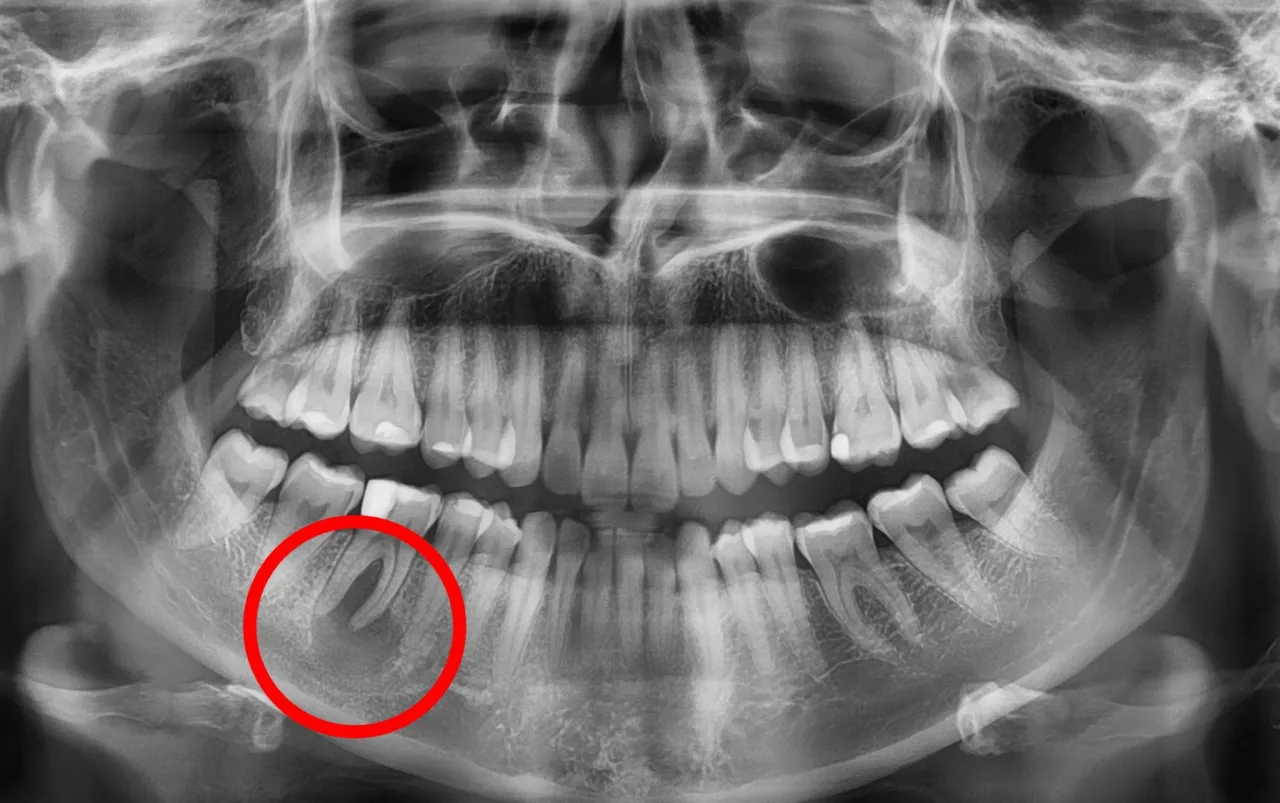

Podstawą diagnozy torbieli jest wizyta u stomatologa, który przeprowadzi dokładne badanie jamy ustnej. Jednak sam ogląd i palpacja często nie wystarczą, aby ocenić charakter i rozmiar zmiany, zwłaszcza jeśli znajduje się ona przy korzeniu zęba. Dlatego kluczową rolę odgrywa diagnostyka obrazowa. Podstawowym badaniem jest zdjęcie rentgenowskie pantomograficzne (obejmujące całe uzębienie) lub punktowe (skupione na konkretnym zębie). Pozwala ono uwidocznić zmiany kostne wokół wierzchołka korzenia, które są typowe dla torbieli.

Kiedy konieczna jest bardziej zaawansowana diagnostyka, np. tomografia?